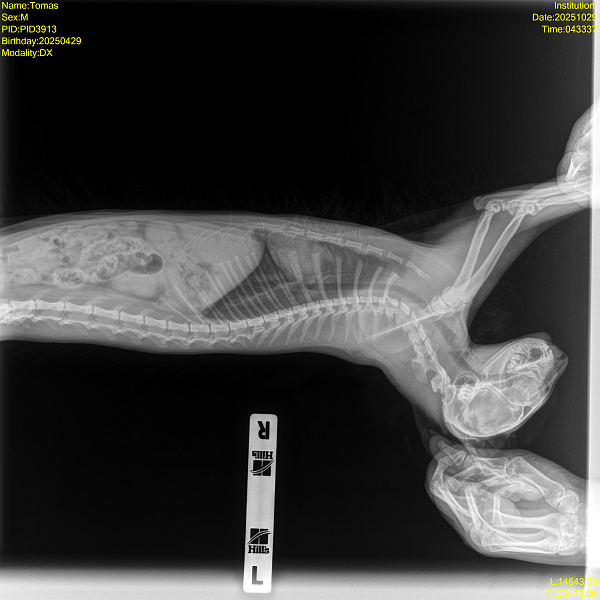

Рентген - смотрел кардиолог, сказал ничего патологического не видит, но может лучше показать пульмонологу для второго мнения.

Прикладываю заключение узи, рентген и видео.

Здравствуйте, дыхание с открытым ртом у кошек при активной физической активности и сильном беспокойстве это может быть вариантом нормы, а вот кашель нет. Наиболее частые причины кашля у кошек это бронхит и астма, дифференцировать эти состояния по рентгену невозможно. Если приступы кашля становятся частыми, то для уточнения диагноза назначают дополнительную диагностику - КТ грудной полости, бронхоальвеолярный лаваж. Если нет возможности провести такую диагностику, то начинаются эмпирическую терапию, чаще всего с ингаляций.

на Ваших снимках выраженных изменений в грудной полости нет, но нельзя исключать, что при сохранении симптомов особенно в виде кашля изменения появятся со временем, если речь идет о формирующейся хронической проблеме. Поэтому если кашель сохраняется, то снимок нужно повторять через 2-6 месяцев.